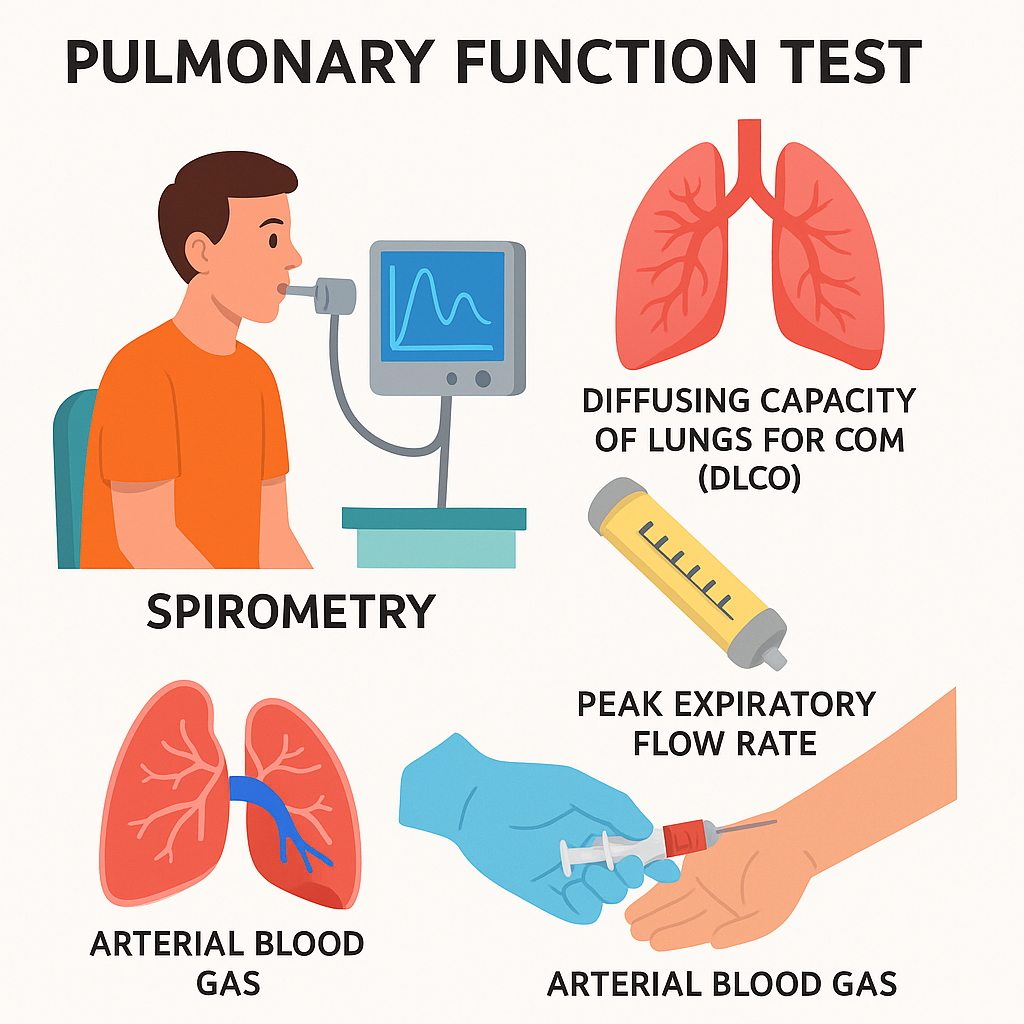

Pulmonary function test (પલ્મોનરી ફંકશન ટેસ્ટ):

- પલ્મોનરી ફંકશન ટેસ્ટ એ ગ્રુપ ટેસ્ટ છે.જે લંગ કેટલી સારી રીતે વર્ક કરે છે તે મેઝર કરે છે.

- જેમાં સ્પાયરોમેટ્રી, લંગ ડીફ્યુઝન ટેસ્ટ, લંગ વોલ્યુમ ટેસ્ટ અને એક્સરસાઇઝ ટેસ્ટનો સમાવેશ થાય છે.

- પલ્મોનરી ફંકશન ટેસ્ટ એ લંગ વોલ્યુમ, કેપેસિટી, ફલો રેટ અને ગેસ એક્સચેન્જ મેઝર કરે છે.

- પલ્મોનરી ફંકશન ટેસ્ટનો ઉપયોગ અમુક પ્રકારના લંગ ડીઝીસને ડાયગ્નોસ કરવા માટે થાય છે. જેમકે અસ્થમા, એમ્ફાયસેમા

Arterial blood gas analysis (ABGs) (આર્ટીરિયલ બ્લડ ગેસ એનાલાયસીસ):

- આર્ટીરિયલ બ્લડ ગેસ એનાલાયસીસ એ એક ઇમ્પોર્ટન્ટ ડાયગ્નોસ્ટિક મેથડ છે. જે બ્લડમાં રહેલ ઓક્સીજન અને કાર્બન ડાયોક્સાઇડનું લેવલ મેઝર કરવામાં આવે છે તેમજ બ્લડ PH અને બ્લડ બાયકાર્બોનેટનું લેવલ પણ મેઝર કરવા માટે ઉપયોગી છે.

- જેમાં મુખ્યત્વે એક્સપર્ટ હેલ્થ કેર પર્સનલ દ્વારા રેડિયલ આર્ટરીમાંથી બ્લડ કલેક્ટ કરવામાં આવે છે આ ઉપરાંત ઘણીવાર બ્રેકીઅલ અથવા ફીમોલર આર્ટરીમાંથી પણ બ્લડ કલેક્ટ કરવામાં આવે છે. (વેઇનમાંથી બ્લડ કલેક્ટ કરવામાં આવતું નથી)

- આ ટેસ્ટ દ્વારા લંગની બ્લડમાં ઓક્સિજન ડીઝોલ્વ કરવાની અને બ્લડમાંથી કાર્બન ડાયોક્સાઇડને રીમુવ કરવાની કેપેસિટી કેટલી છે તે જાણી શકાય છે.

- આ ટેસ્ટ કરતા પહેલા એલેન ટેસ્ટ કરવામાં આવે છે જે હેન્ડમાં બ્લડ સપ્લાય કરતી આર્ટરીની (રેડીયલ અને અલ્નાર આર્ટરી) પેટેન્સી ચેક કરવા માટે વપરાય છે. Normal value of ABGs (નોર્મલ વેલ્યુ ઓફ ABGs)